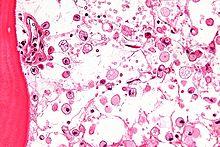

Micrograph showing crinkled paper macrophages in the marrow space in a case of Gaucher disease, H&E stain.

Gaucher disease is suggested based on the overall clinical picture. Initial laboratory testing may include enzyme testing. As a result, lower than 15% of mean normal activity is considered to be diagnostic.[23] Decreased enzyme levels will often be confirmed by genetic testing. Numerous different mutations occur; sequencing of the beta-glucosidase gene is sometimes necessary to confirm the diagnosis. Prenatal diagnosis is available and is useful when a known genetic risk factor is present.

A diagnosis can also be implied by biochemical abnormalities such as high alkaline phosphatase, angiotensin-converting enzyme, and immunoglobulin levels, or by cell analysis showing "crinkled paper" cytoplasm and glycolipid-laden macrophages.

The disease is caused by a defect in housekeeping gene for lysosomal glucocerebrosidase (also known as beta-glucosidase, EC 3.2.1.45, PDB: 1OGS​) on the first chromosome (1q22). The enzyme is a 55.6-kilodalton, 497-amino acid-long protein that catalyses the breakdown of glucocerebroside, a cell membrane constituent of red and white blood cells. In Gaucher disease, the enzyme is unable to function correctly and glucocerebroside accumulates. The macrophages that clear these cells are unable to eliminate the waste product, which accumulates in fibrils, and turn into 'Gaucher cells', which appear on light microscopy to resemble crumpled-up paper.[3]